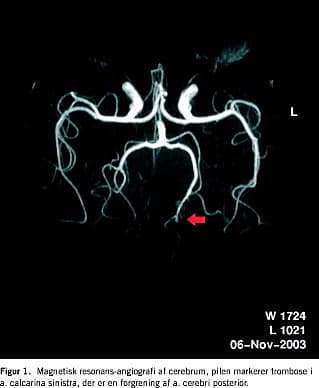

Ved en synsfeltsundersøgelse ved kampimetri blev der fundet massiv højresidig homonym hemianopsi med makulær sparring. I øvrigt blev der fundet normale forhold ved øjen-undersøgelse. Blodtrykket ved indlæggelsen var på 150/100, og ved senere målinger var det normaliseret til 130/80. Patienten blev udredt paraklinisk for bl.a. hyperviskositetsyndrom og hyperkoagulable tilstande, og blodprøveværdierne inklusive værdierne for trombocytter, koagulationsfaktorer, antitrombin, aktiveret partiel tromboplastintid (APTT), protein C, protein S, lupusantikoagulans, kardiolipinantistof, homocystein, kolesteroltal og blodsukker lå inden for normalområdet. En computertomografi af cerebrum viste iskæmisk infarkt i venstre occipito-parietale region. En magnetisk resonansangiografi af de cerebrale kar og aa. carotides viste en okklusion af a. calcarina sinistra, der er en forgrening af a. cerebri posterior (Figur 1 ). Ved undersøgelsen blev der i øvrigt fundet normale arterier både intracerebralt og i aa. carotides, dvs. at der ikke var atrioventrikulære malformationer, aneurismer eller cerebral aterosklerose, som kunne forklare patientens symptomer. Ved elektrokardiogram og ekkokardiografi blev der fundet normale forhold, og ved en transøsofageal ekkokardiografi sås der ingen tegn på persisterende foramen ovale, og der var således ingen holdepunkter for kardial embolikilde.